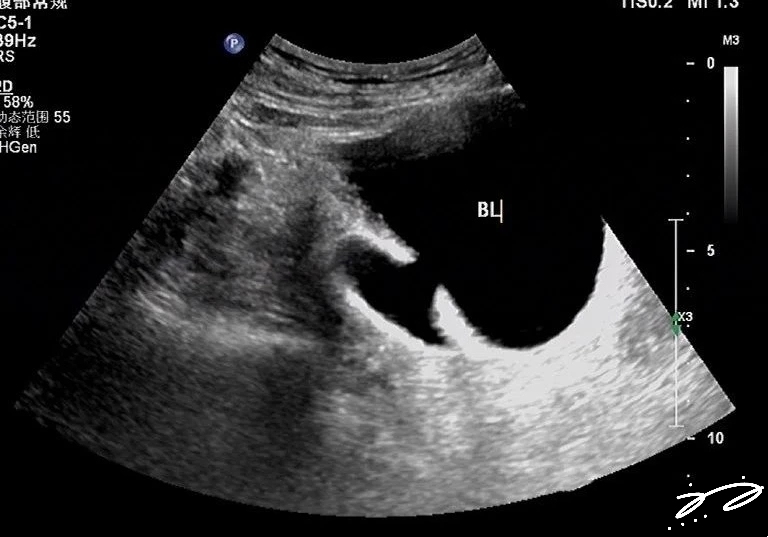

膀胱憩室

图片尺寸1920x1080